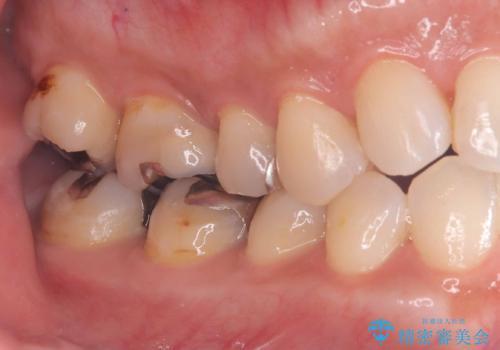

- 銀歯と歯の間に穴があり虫歯になっていました。

銀歯と虫歯を除去後、オールセラミッククラウンで治療を行いました。

銀歯のほとんどは錆びる金属で出来ています。

銀歯を外すと大小様々ですが、そのほとんどが虫歯になっていることが多いです。

今回も虫歯は大きく神経の近くまで広がっていましたが、神経は取らずに治療を終えることが出来ました。